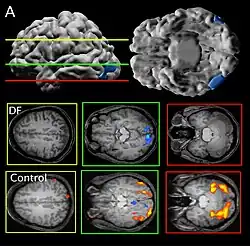

Patient DF's brain damage resulted from hypoxia due to accidental carbon monoxide poisoning in 1988, when she was 34 years old.[2] The lateral occipital cortex (LOC) in her brain is severely damaged and shows no activation presented with line drawings of common objects where healthy people usually do. Moreover, there is a reduction of white matter connections between LOC and other areas.[3] There is also some shrinkage in the intraparietal sulcus, often implicated in the dorsal stream for visuomotor control. The fusiform face area is intact. This would suggest the problem in DF's perception is disconnectivity between higher and lower order functioning.[4]

Recent MRIs have shown many enlarged sulci, like the intraparietal sulcus, parieto-occipital sulcus, and left calcarine sulcus, indicating atrophy.[4] Her visual field remains intact up to 30 degrees.[1]

DF does not benefit from haptic feedback—allowing her to pick up an object does not let her better estimate its width next time.[5] DF also does not use visual information about her grasp: when she can only see her grip in a distorted mirror, her performance does not change.[4] Consistent with all of this, brain imaging has shown no response to line drawings in her ventral stream. Furthermore, according to fMRI studies, the intraparietal sulcus showed preference for grasping motions over reaching motions—actually grabbing an object, in both DF and control patients, activates the intraparietal sulcus more than reaching.[4]